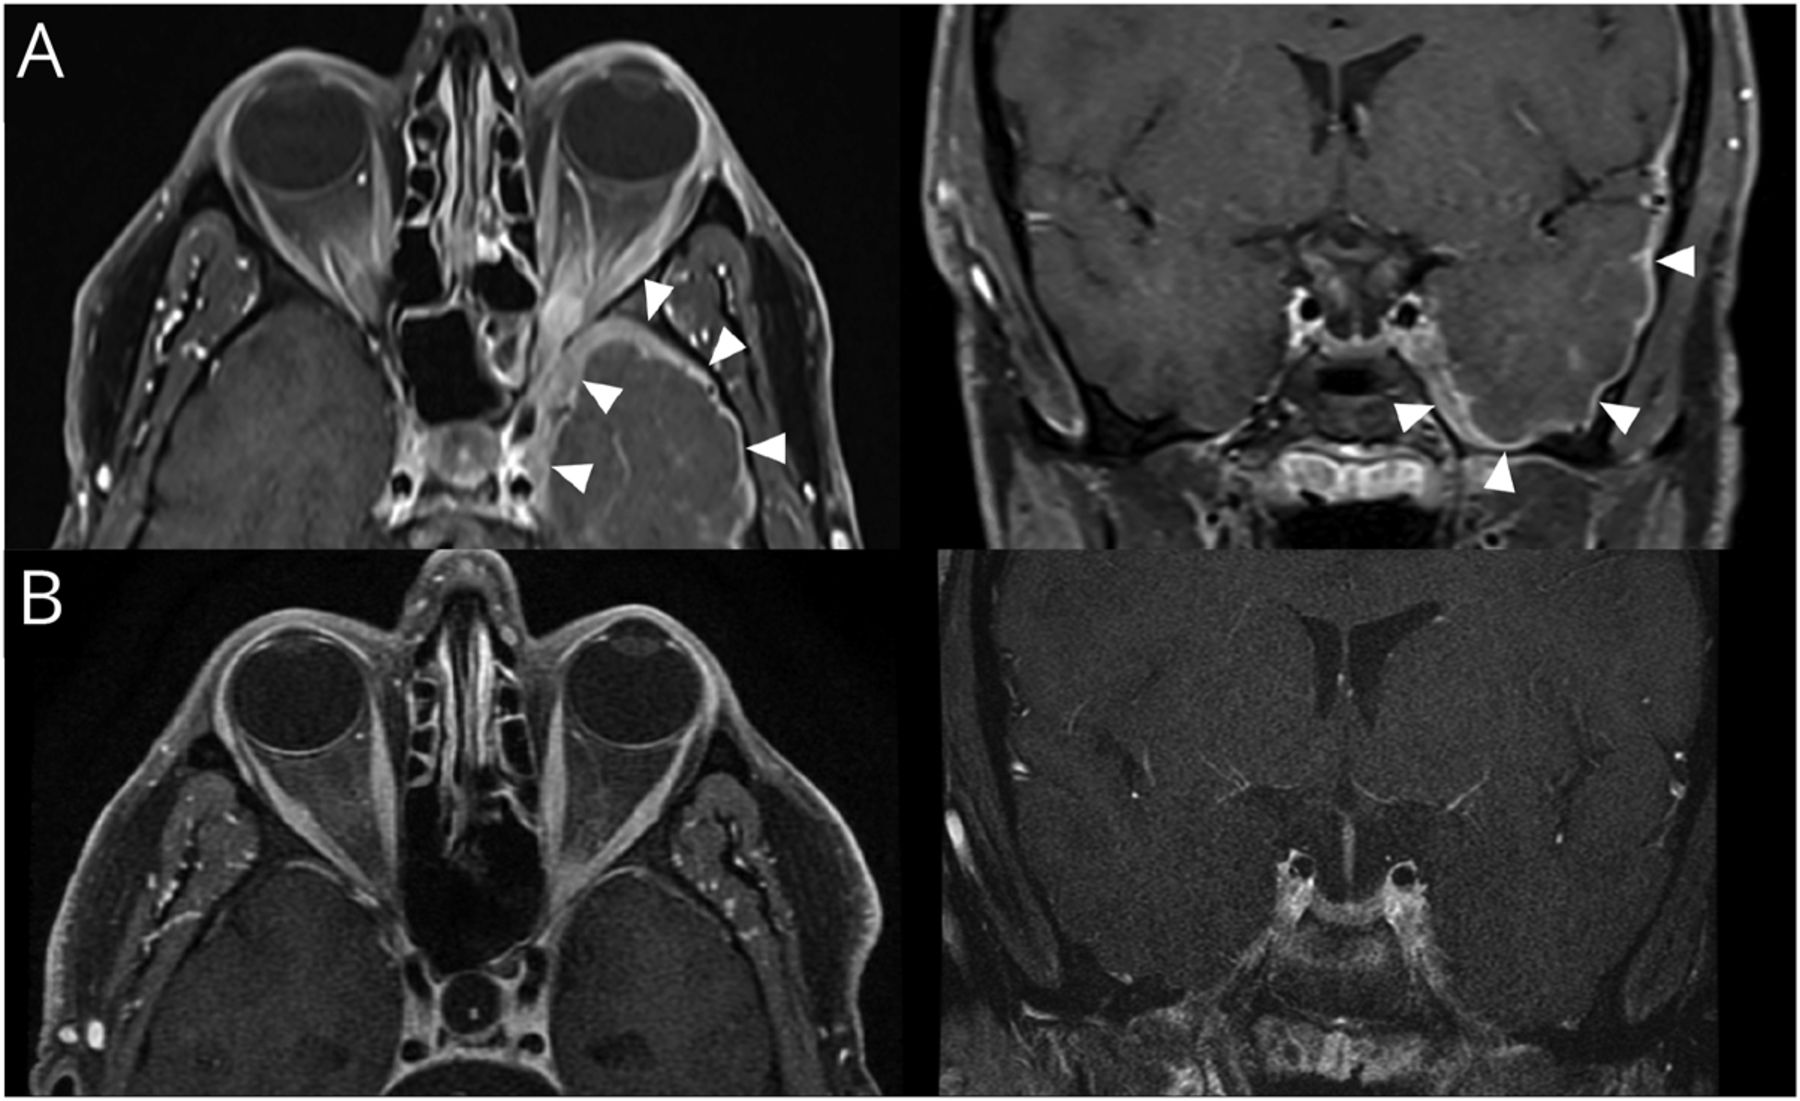

图2

图2 核磁共振的轨道

(一)对比MRI显示增强的左外侧直肌和轨道顶端跟踪后方左侧海绵窦和颅内硬脑膜的扩展中颅窝(箭头)。(B)对比MRI 6个月后,与缓慢的锥度,大剂量糖皮质激素后显示完整的增强分辨率和横向腹直肌增大。

神经外科勘探被认为是过于侵入性,相反,一个左横向腹直肌和眶脂肪垫活检是追求,显示非特异性炎症变化和温和的慢性炎症,显示结果为恶性肿瘤,血管炎,或IgG4-related疾病。在医院,他的视力下降了20/200的操作系统,所以他对待经验1 g的IV脉冲连续5天每天甲强龙,紧随其后的是60毫克每日口服强的松。他的痛苦决定,他在临床及影像上逐步改善(图2 b)。在1月,突出和相对瞳孔传入障碍解决了持久的瞳孔大小不等。视力是OD 20/20和20/60 OS,他的眼外的动作都是在垂直距离,稍微受到绑架和内收的5%。强的松在慢慢锥形超过2个月。在24个月,他和20/20的双眼视力保持无症状,轻度残余exodeviation测量2棱镜度在正确的目光。